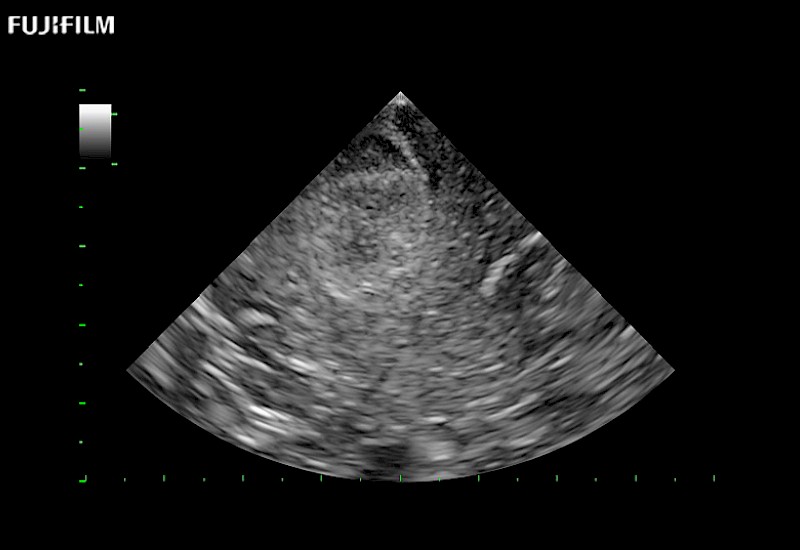

Our dedication to neurosurgery allows us to offer superior image quality, outstanding system reliability and intuitive use of cutting edge technology.

Guidance is the fundamental purpose for all of our surgical ultrasound technology. Fujifilm Healthcare is committed to designing tools that help neurosurgeons navigate inside the human body and provide the necessary information to immediately make critical surgical decisions.